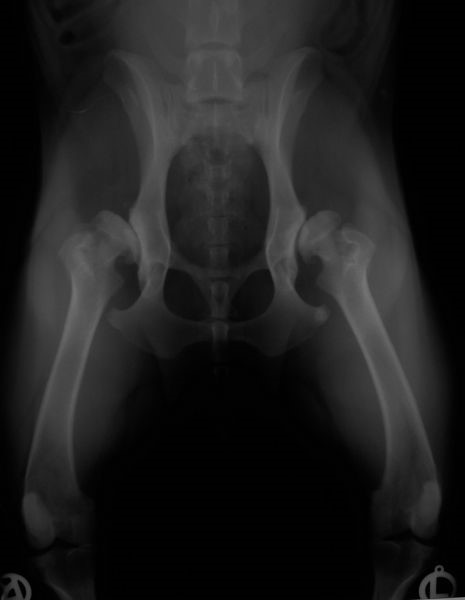

Zadaniem badania radiologicznego jest ocena nadwichnięcia główek kości udowych i stopnia zwyrodnienia stawów biodrowych. Istnieje wiele metod ułożenia pacjenta i oceny radiogramów. Najpopularniejszą i obecnie obowiązującą w Polsce metodą jest metoda zaproponowana przez OFA ( Orthopedic Fundation for Animals )

Początkowo stwierdza się nieznaczne spłycenie panewki. Jednym z pierwszych objawów dysplazji jest zmiana zarysu doczaszkowej krawędzi panewki. Traci ona swój ostry trójkątny kształt i staje się zaokrąglona. Powoduje to poszerzenie bocznej okolicy szpary. Dalszymi charakterystycznymi objawami są poszerzenie przyśrodkowej okolicy szpary stawu biodrowego i zmniejszone pokrycie głowy kości udowej przez krawędź panewki. W wyniku zmienionych warunków mechanicznych następuje przebudowa i zmiana kształtu głowy i szyjki kości udowej. Zarys głowy staje się zbliżony do kwadratu. Szyjka staje się mniej smukła, grubsza, traci wcięcie i robi wrażenie krótszej. Równolegle rozwijają się w stawach biodrowych zmiany zwyrodnieniowo-wytwórcze z tworzeniem się osteofitów na krawędziach panewki, głowie i szyjce kości udowej. W najcięższych przypadkach panewka jest tak płytka, że nie obejmuje ona głowy kości udowej i nie utrzymuje jej we właściwym położeniu, co prowadzi do patologicznego zwichnięcia stawu biodrowego.

Skrajna dysplazja stawów biodrowych